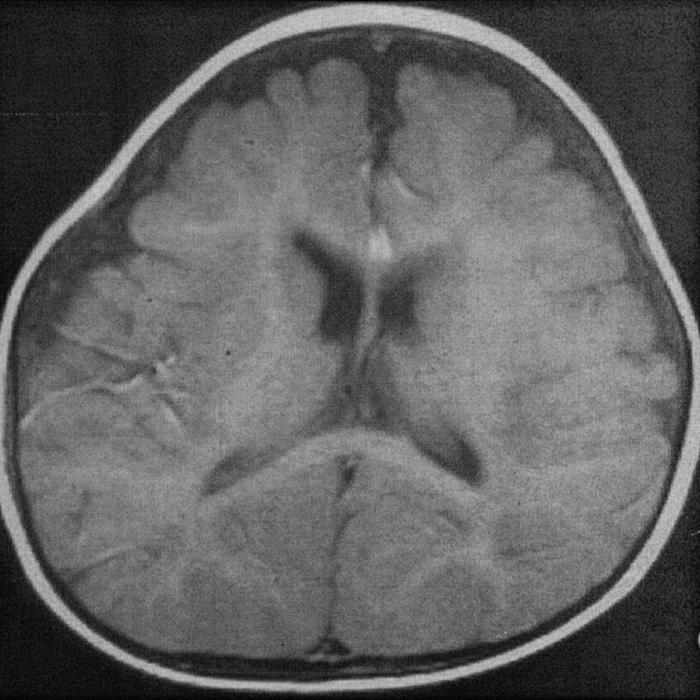

Наружная заместительная гидроцефалия головного мозга (народное название «водянка») – распространенная патология, которая приводит к нарушению работоспособности центральной нервной системы. В результате у пациента наблюдается всасывание церебральной жидкости в данный орган.

Также данная патология может спровоцировать уменьшение размеров головного мозга, а пространство, которое стало свободным и заполняется данной жидкостью. Заместительная гидроцефалия может развиваться практически бессимптомно на протяжении длительного периода времени.

Данный вид гидроцефалии, как и любой другой, развивается в результате накопления церебральной жидкости в полостях головного мозга. В результате у пациента отмечается повышенное давление внутри черепа, происходит интенсивное давление на мозговое вещество и уменьшается пространство между арахноидальной и мягкой оболочкой мозга.